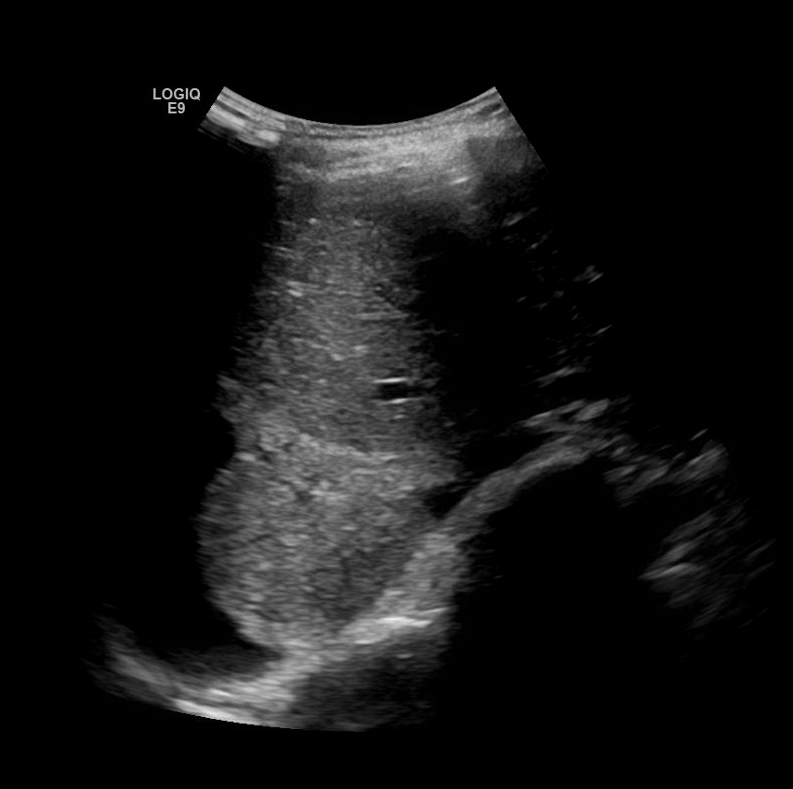

Consolidation

Hepatization of the lung parenchyma due to infiltration with fluid. May also have “air-bronchograms”.

Color doppler will show blood flow through the pulmonary vasculature.

Consolidation/Atelectasis

In alveolar consolidation the lung parenchyma takes on the appearance of liver echotexture, “hepatization”. There may be air bronchograms present in consolidated tissue which appears as hyperechoic air bubbles with reverberation artifacts. Color doppler will show blood flow through the pulmonary vasculature.